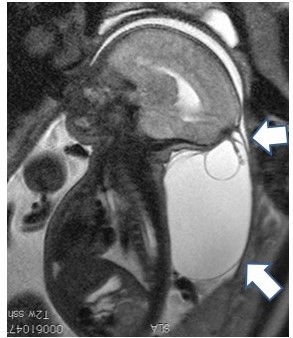

脳瘤はしばしば頭蓋顔面奇形や中枢神経の奇形を伴います。特に水頭症を認める例が多くみられます。脳瘤は通常後頭部に比較的大きな瘤(図1、MRI、矢印)を認めていますが、停止性脳瘤と呼ばれる頭皮の小さな病変(図2、矢印)や頭蓋底脳瘤と呼ばれる、鼻腔内に瘤が突出するような例はCT、MRIで診断されます。瘤に一致した部分の頭蓋骨に孔が開いていることが脳瘤の特徴です。また頭蓋底に脳瘤がある場合には、鼻腔を閉塞することで気道が通りづらくなることがあります。

図1 後頭部脳瘤のMRI 嚢胞を後頭部に認めている